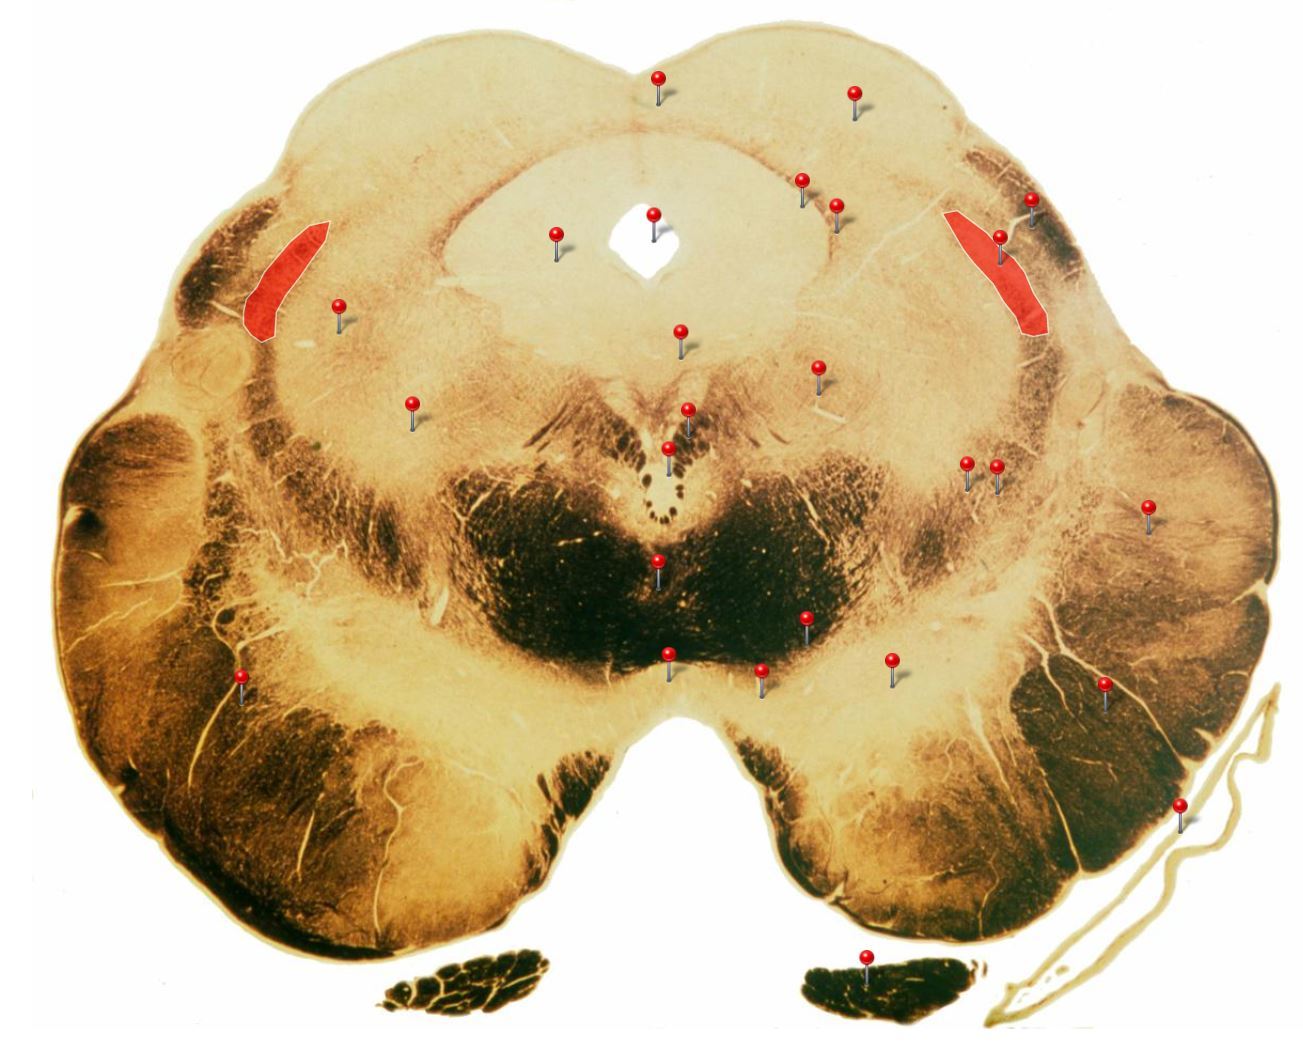

Caudal Midbrain

Transmits auditory info from the inferior colliculus to the medial geniculate nucleus of the thalamus

Edinger Westphal Nucleus

Oculomotor Nerve (CN III)

Supplies extraocular muscles (4 out of the 6; levator palpebrae of upper eyelid, ciliary and sphincter pupillae of the eye)

Corticospinal Tract

Controls precision and speed of skilled movements involving the distal muscles of the contralateral limbs, particularly those of the hands and fingers

5

Q

Rubrospinal Tract

Assists in the control of movements of the hands and fingers

6

Oculomotor Nucleus

Neurons give rise to GSE fibres of the oculomotor nerve (CN III) which supply extraocular muscles (4 out of the 6, as well as some fibres of the levator palpebrae superioris m.)

7

Spinothalamic Tract

Transmits pain and temperature sensations from the spinal cord to the thalamus

8

Superior Colliculus

Important relay centre for visual reflexes

9

Periaqueductal Gray (PAG)

Important centre in modulating pain transmission in the spinal cord, particularly in conditions of extreme stress (indirectly through connections with reticular formation)

10

Medial Longitudinal Fasciculus

Pathway through which eye movements are coordinated with changes in head position